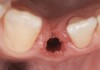

Problem: The implant is placed too facially, and there is significant labial gingival recession, contour change, and mucosal discoloration around the implant, abutment, and crown (Figure 3 and Figure 4). The implant attachment apparatus is intact and healthy, but the patient has a thin periodontal phenotype.

The following case report provides an example of this case scenario: A 28-year-old white female patient presented with her maxillary right lateral incisor significantly longer than the contralateral tooth following restoration of an existing crown that was 10 years old (Figure 3). The patient was dissatisfied with the esthetic appearance of the restoration due to the increased length, recession of the gingival tissues, and discoloration of the surrounding mucosa (Figure 4). Similar to case scenario No. 1, the first step in treatment was to decoronate the healthy implant by placing a flat surgical cover screw and employing a provisional resin-bonded-retained (RBR) prosthesis as a transitional fixed restoration (Figure 5 and Figure 6). The gingival augmentation in situ was allowed to take place for 2 to 3 weeks and was evaluated after that time (Figure 7).

Fig 3. A patient presented with a high smile line and midfacial recession of the maxillary right lateral incisor as evidenced by the increased tooth length compared with the contralateral lateral incisor.

Fig 4. Intraoral view of tooth No. 7 with the gingival zenith more apical than the adjacent central incisor and canine tooth.